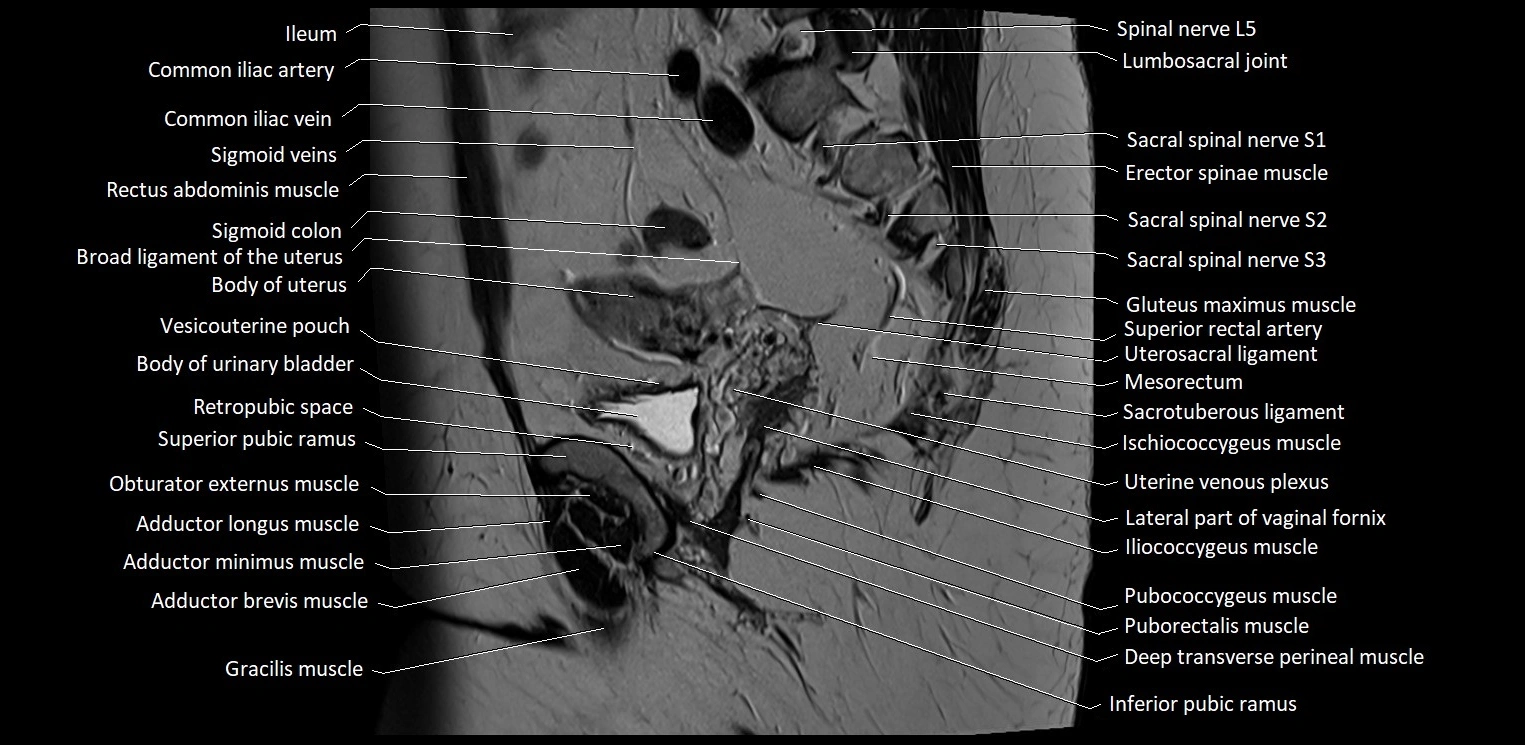

- Adductor brevis muscle

- Adductor longus muscle

- Adductor minimus muscle

- Body of urinary bladder

- Body of uterus

- Broad ligament of uterus

- Common iliac vein

- Deep transverse perineal muscle

- Gracilis muscle

- Ileum

- Iliococcygeus muscle

- Inferior pubic ramus

- Lumbosacral joint

- Mesorectum

- Obturator externus muscle

- Pubococcygeus muscle

- Puborectalis muscle

- Pyramidal muscle (pyramidalis muscle)

- Retropubic space

- Sacrotuberous ligament

- Sartorius muscle

- Sigmoid colon

- Spinal nerve L5

- Spinal nerve S2

- Spinal nerve S3

- Superior rectal artery

- Uterosacral ligament

- Vagina

- Vesicouterine pouch